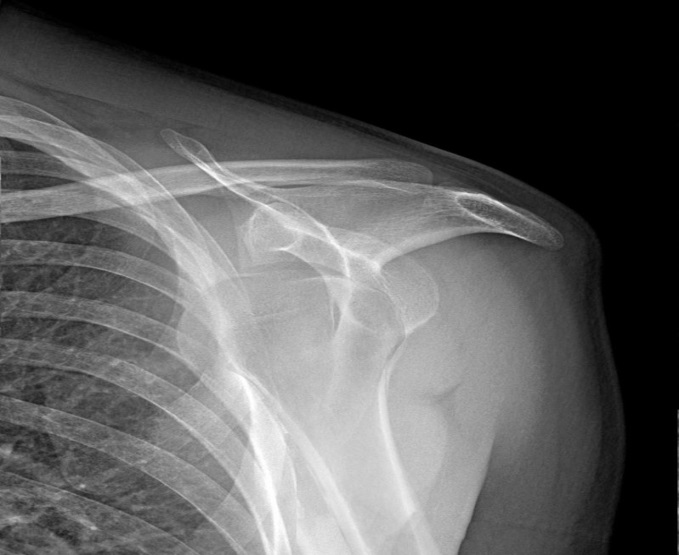

effective treatment. We present a case of a 24-years-old woman who diagnosed

with left shoulder dislocation and fracture secondarily to generalized tonic

clonic seizure due to acute INH intoxication. The patient who was referred to